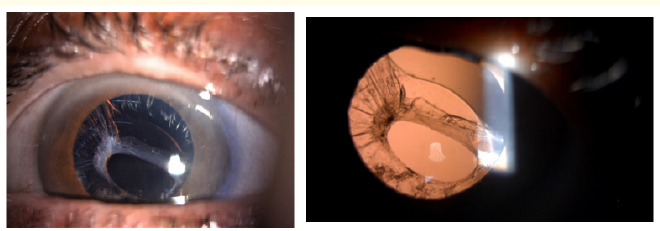

Clinical Image

Iris Mammillations without Ocular Melanocytosis in a Young Patient

Farah Benlkadri, El Mehdi El Filali, Basma Ouidani, Youssef Bennouk, Hussein Ait lhaj, Mohamed Kriet and Fouad Elasri. 14(9): 01-02.